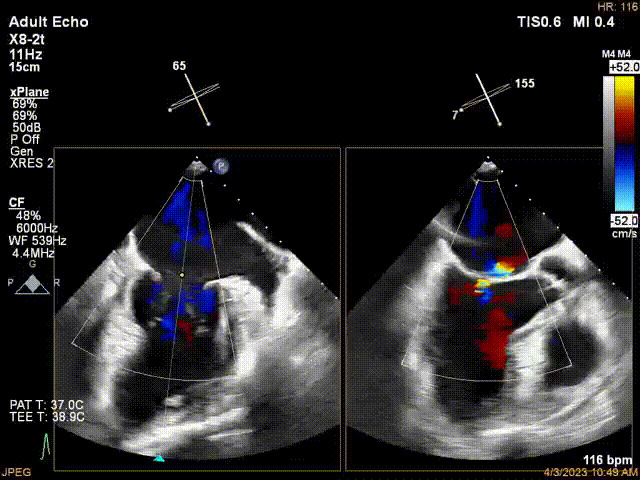

接受治療的是一例器質(zhì)性重度二尖瓣反流(DMR)患者,主訴“反復(fù)活動(dòng)后胸悶,氣促3年余”。術(shù)前超聲顯示,雙房增大,二尖瓣脫垂伴重度反流,輕度三尖瓣反流,輕度肺高壓,升主動(dòng)脈增寬。手術(shù)經(jīng)股靜脈-房間隔入路,采用全身麻醉插管,在TEE和DSA引導(dǎo)下完成房間隔穿刺。置入JensClip瓣膜夾系統(tǒng)后,在左房調(diào)整瓣膜夾的位置和軸向,后進(jìn)入左室,在TEE引導(dǎo)下捕捉二尖瓣前后瓣葉,并關(guān)閉瓣膜夾。經(jīng)TEE反復(fù)確認(rèn)手術(shù)效果后最終鎖定并釋放瓣膜夾。術(shù)后即刻超聲顯示瓣膜夾位置穩(wěn)定,功能良好,術(shù)前二尖瓣反流4+,術(shù)后0反流,肺靜脈逆流和左房壓都顯著好轉(zhuǎn),手術(shù)圓滿(mǎn)成功(以上數(shù)據(jù)都來(lái)源于醫(yī)院的臨床記錄)。術(shù)后患者狀態(tài)良好,目前已安排出院。

術(shù)后超聲顯示二尖瓣反流消失,瓣膜夾穩(wěn)定